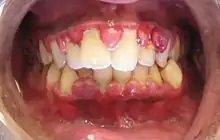

| A severe case of gingivitis | |